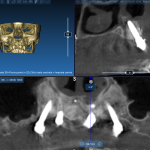

Sopravvivenza di Impianti Core-X® posizionati con chirurgia driver guidata

In questo articolo viene effettuata un’analisi retrospettiva per verificare la sopravvivenza di Impianti Core-X® posizionati con chirurgia driver guidata, con un follow up minimo...